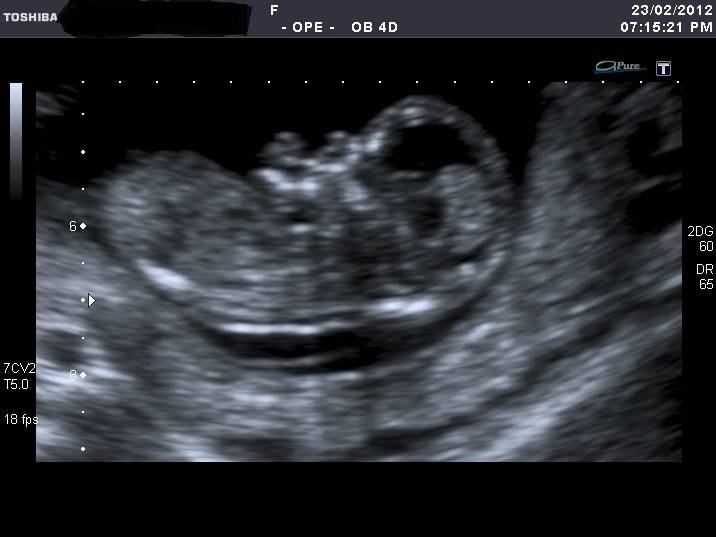

I'm sorry for spaming again with my nub shots, but now when I look at u/s pics I'm not sure I can a see a nub at all????

If you can see it, please enlighten me where to look. Also I think scull looks girly on some pics and boyish on the others.

I was 12 weeks, measuring 12 weeks 5 days